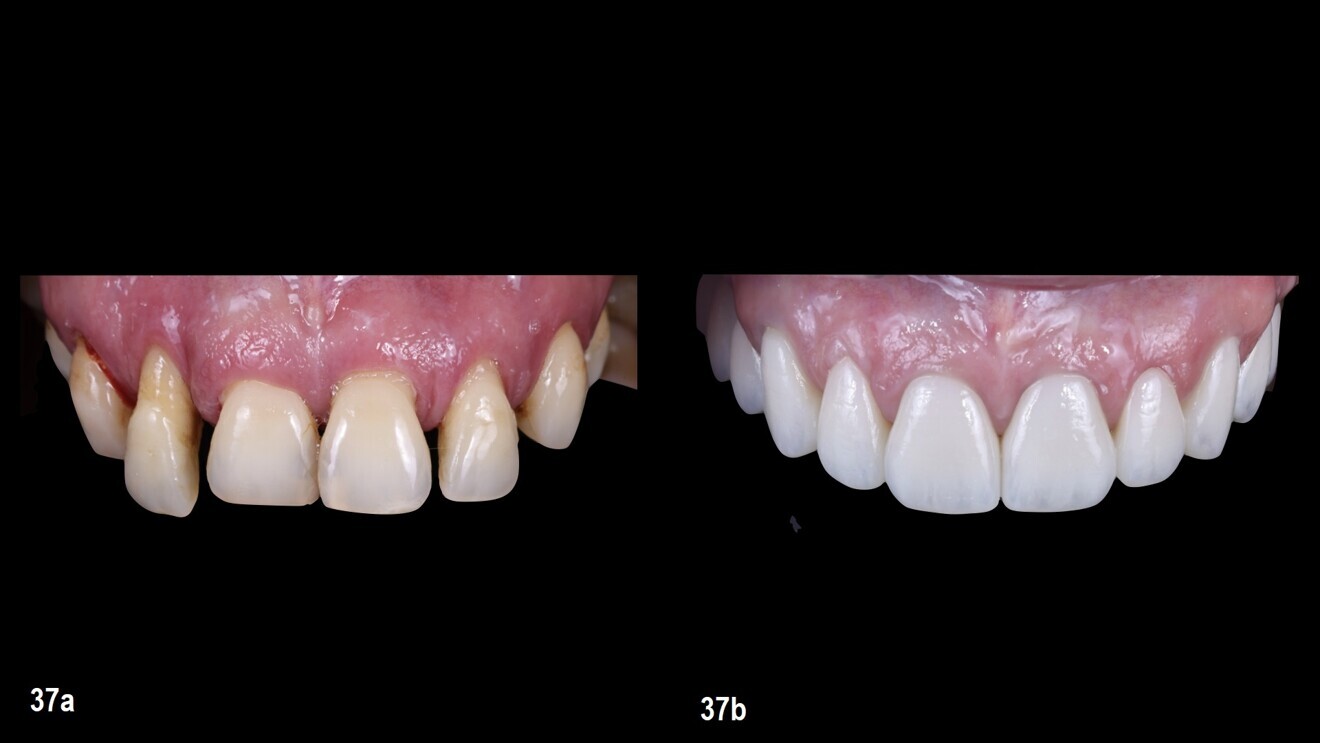

This design strategy, combining precision in planning and soft-tissue management, resulted in a highly aesthetic and functional definitive restoration (Figs. 36a–37b).

Figs. 37a & b: Intra-oral situation before (a) and after the treatment (b)